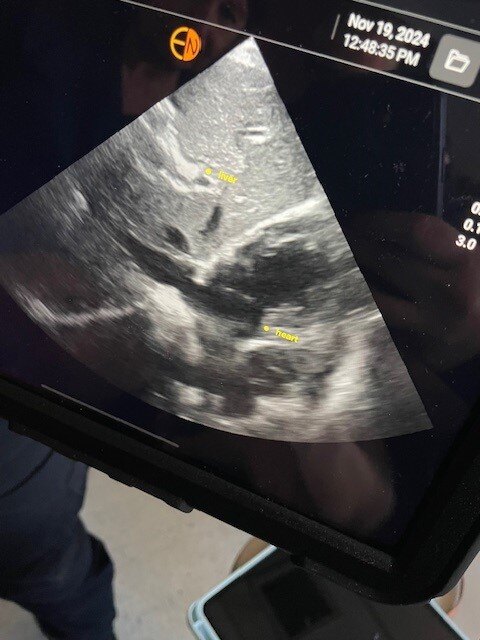

EchoNous ultrasound devices are used by paramedics to find “free fluid,” such as blood, in an individual who has suffered a serious injury. Using the device, paramedics can scan a patient’s body to determine if they are bleeding internally. The technology uses artificial intelligence (AI) to identify organs that are being scanned, allowing first responders to find where a potential injury is.

Discovering an internal bleed as soon as possible can let first responders know if they should transport a patient to a local hospital or a trauma center. In the event of an internal bleed, decreasing the time that a patient is brought to a trauma surgeon impacts survival tremendously. In some cases, a patient may appear to be unhurt, but an ultrasound scan can quickly determine if there is a serious internal injury.